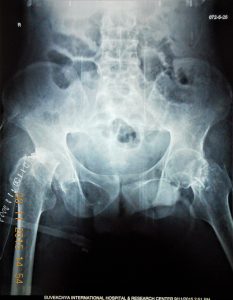

- 1 st Operation X Ray: BL Femoral Neck Osteotomy

- Skeletal Traction for Hip and Knee Release